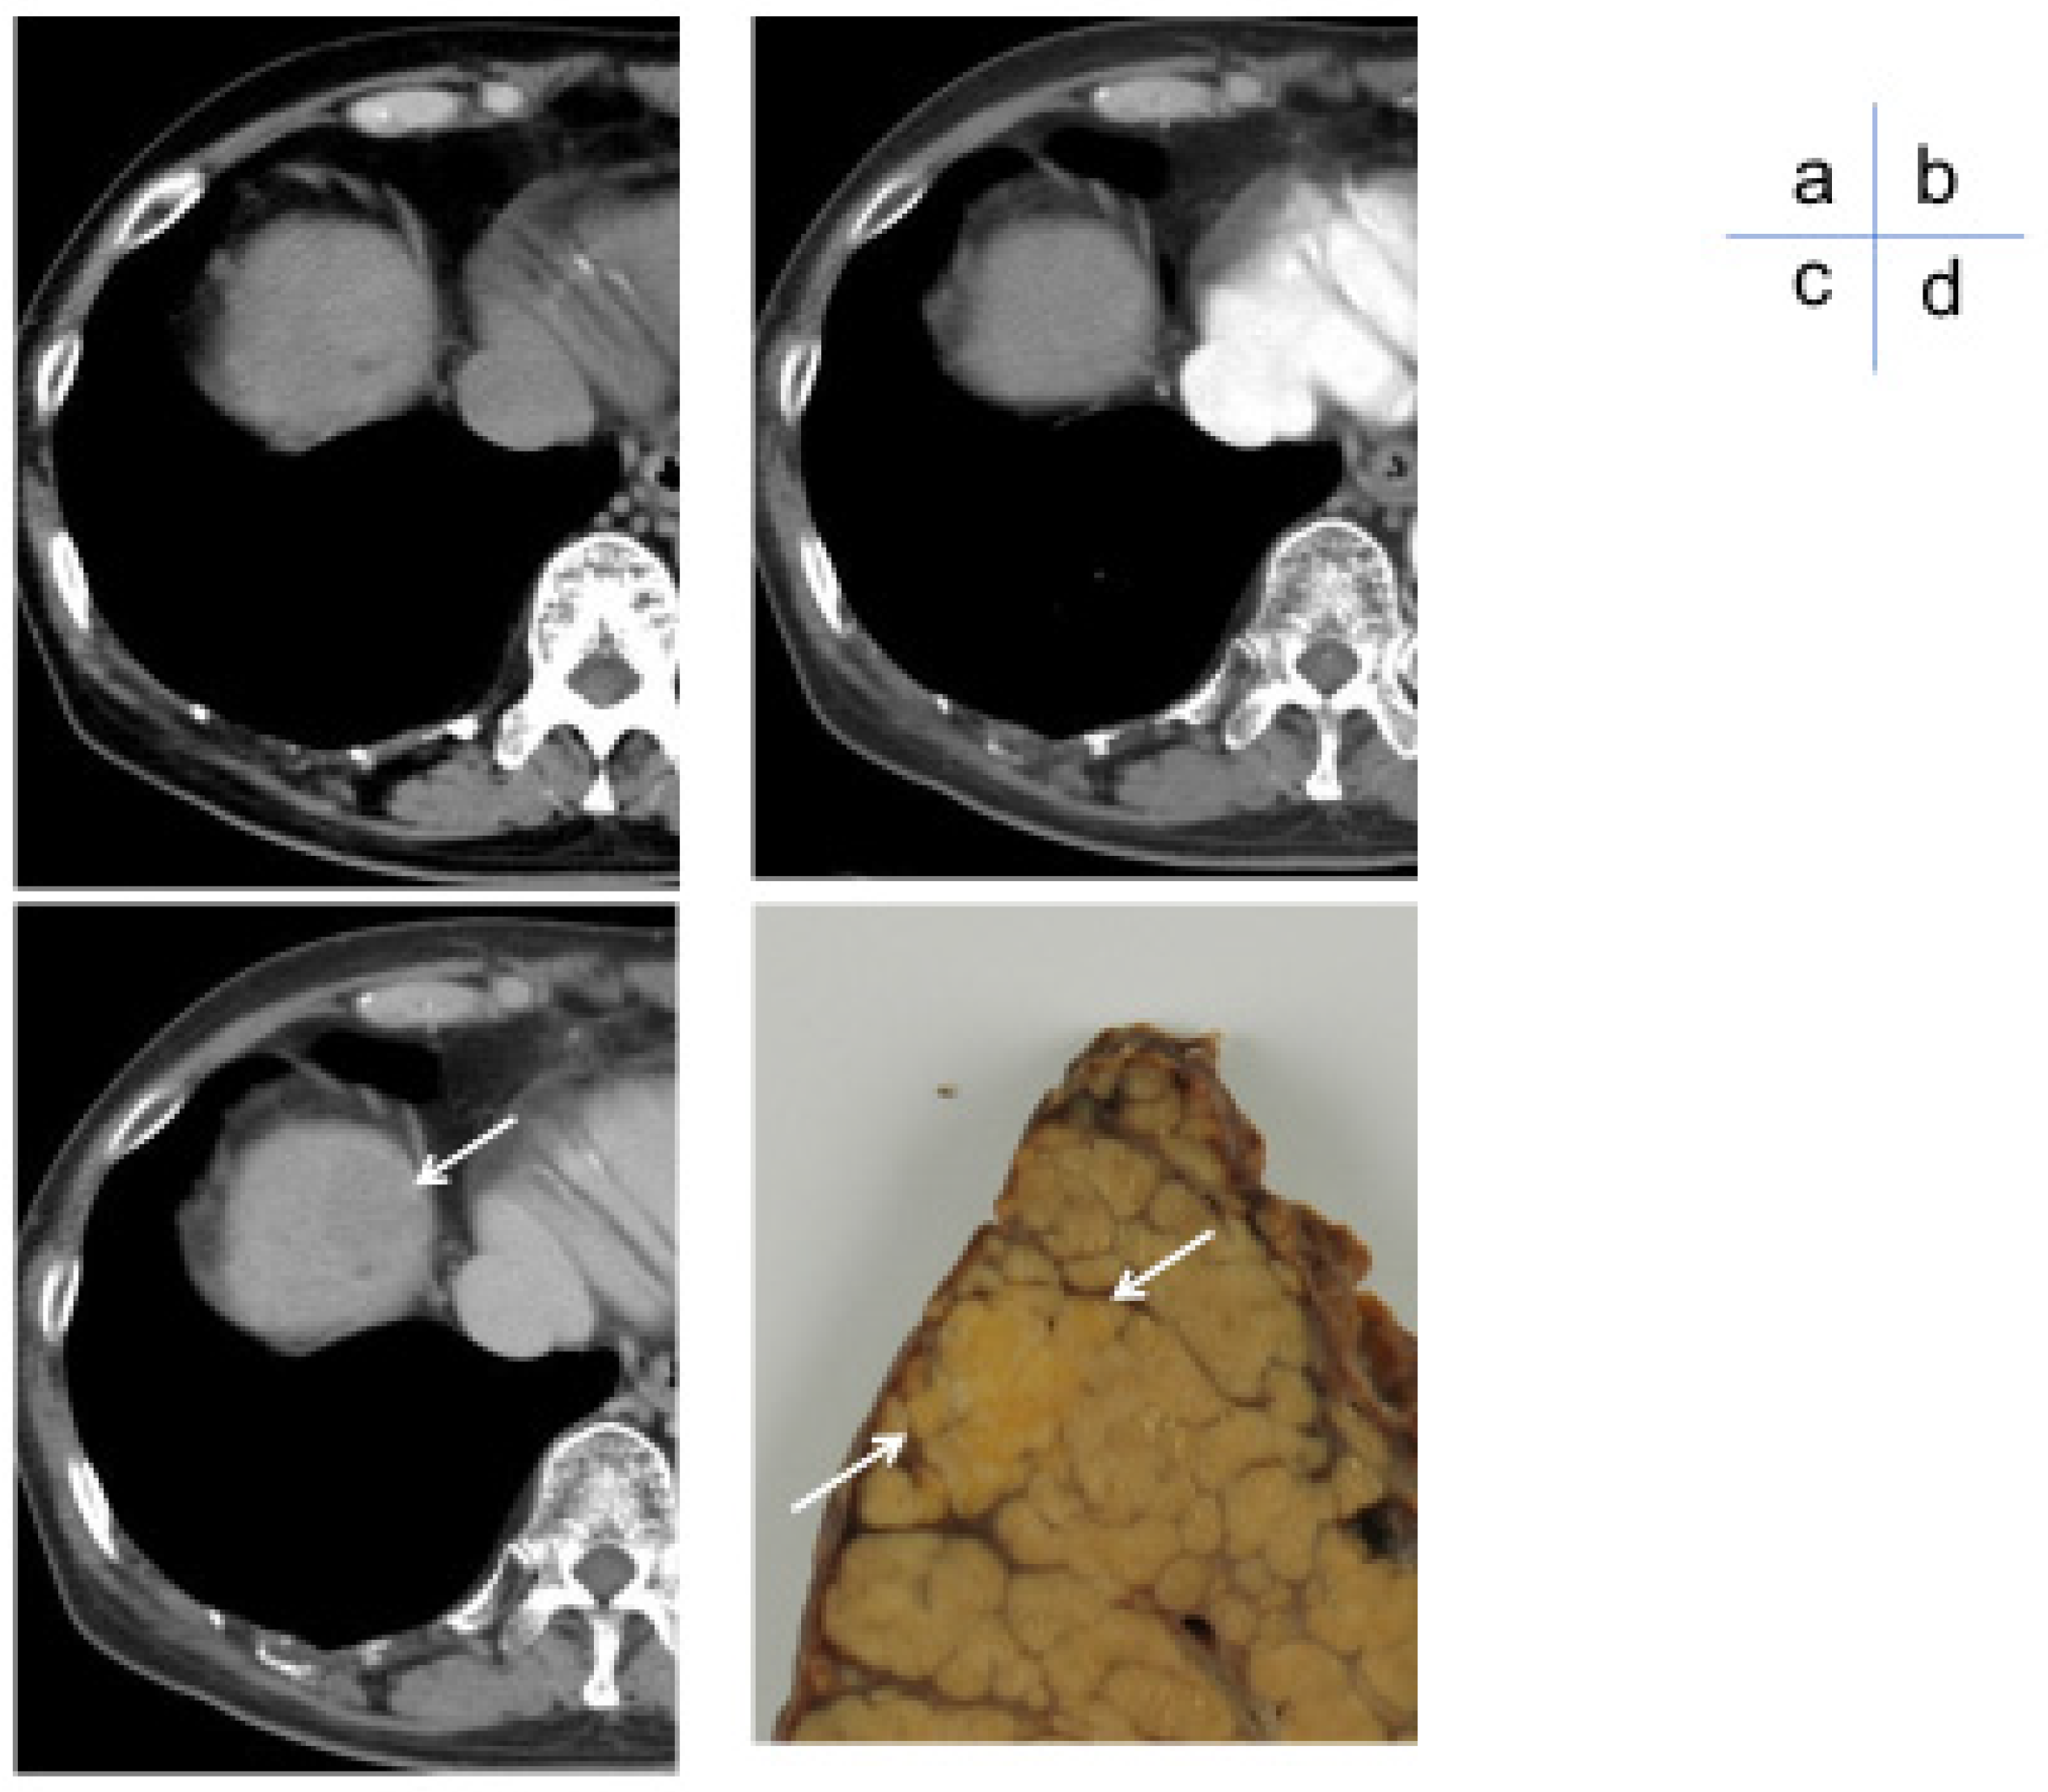

2. Diagnostic Efficacy of Dynamic CT in HCC

3. Role of Dynamic CT/MRI in Differentiating Tumor Grades